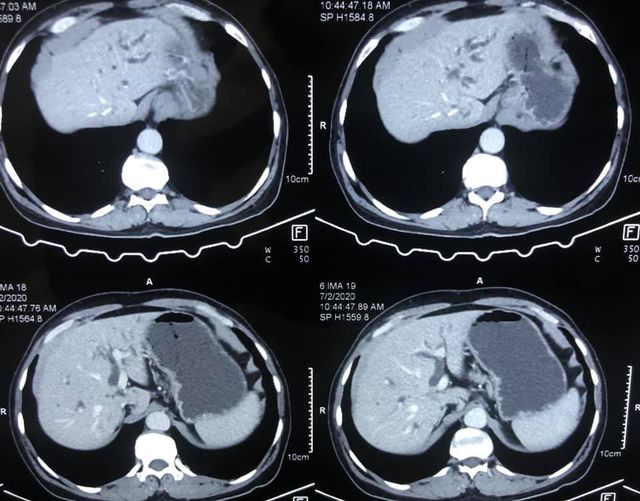

65 years of man type 3A hilar cholangiocarcinoma (complex hepatobiliary malignancy) with deep jaundice

SIX STEPS TO SUCCESS IN A ROLLER COASTER COVID CHALLENGE

- STEP 1: Left PTBD (to bring down jaundice)

- STEP 2: portal vein embolisation to allow growth of the small remnant left liver

- STEP 3: Right sided anterior and posterior PTBD to control persistent fever after initial intervention.

- STEP 4: admitted for surgery COVID positive CT CO-RADs 5 managed medically

- STEP 5: after 3 weeks waiting and repeat COVID PCR negative (couldn’t wait longer for risk of catheter dislodgement while waiting) underwent an Extended Rt hepatectomy with caudate lobectomy bile duct excision Left hepaticojejunostomy

- STEP 6: despite all the trials& tribulations and 7 hr surgery patient had a smooth recovery discharged by D6. An extremely satisfying result in a very difficult malignancy and a super motivated patient.